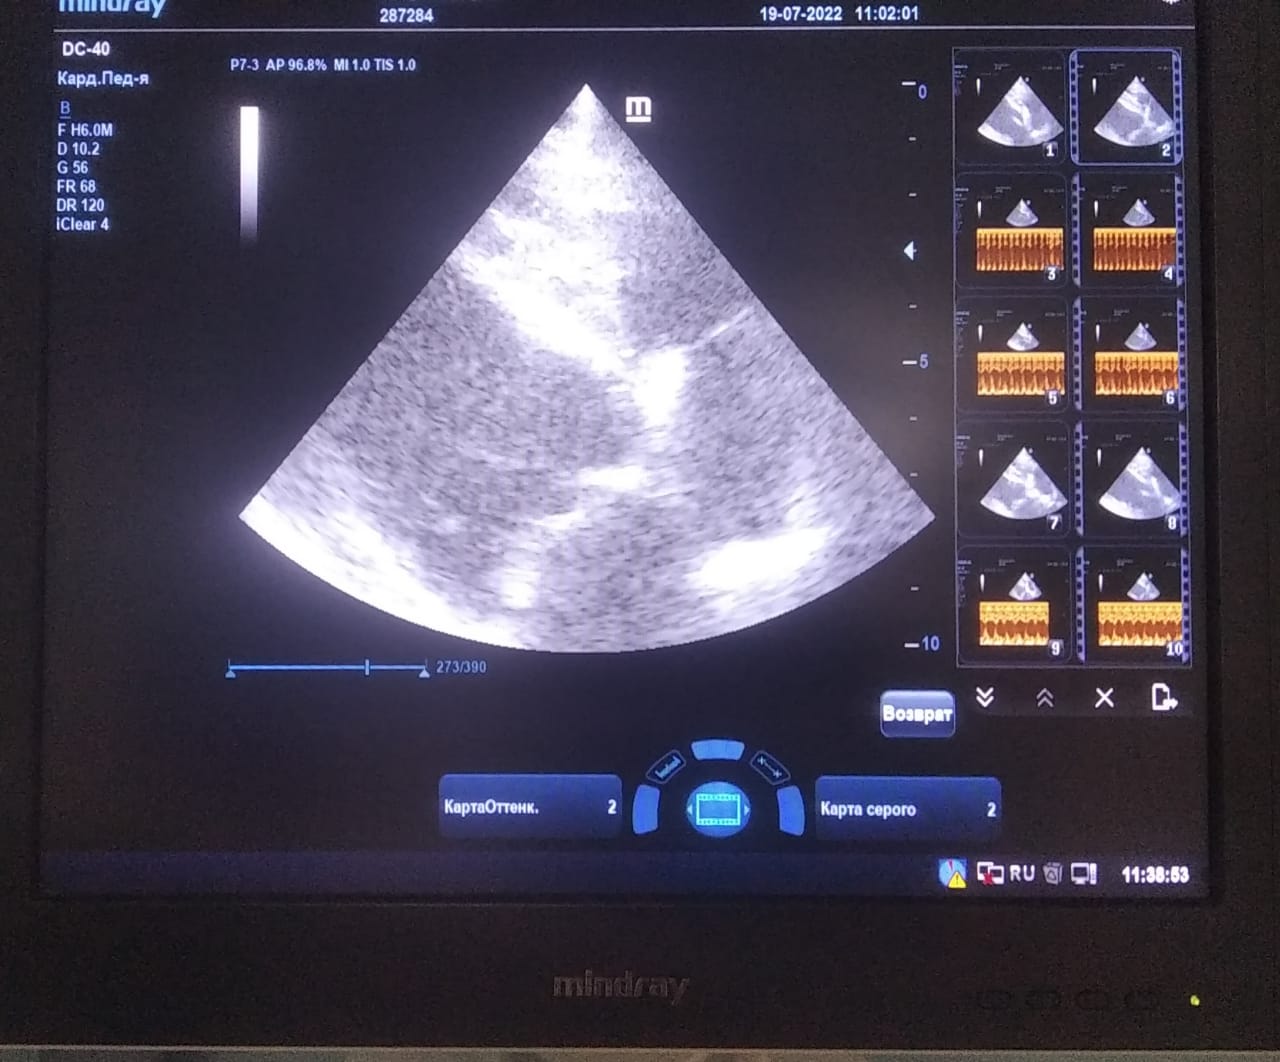

Анализы Арчи. Сердца и легких

Вложения

IMG-20220719-WA0100.jpg

IMG-20220719-WA0102.jpg

IMG-20220719-WA0104.jpg

IMG-20220719-WA0103.jpg

IMG-20220719-WA0105.jpg